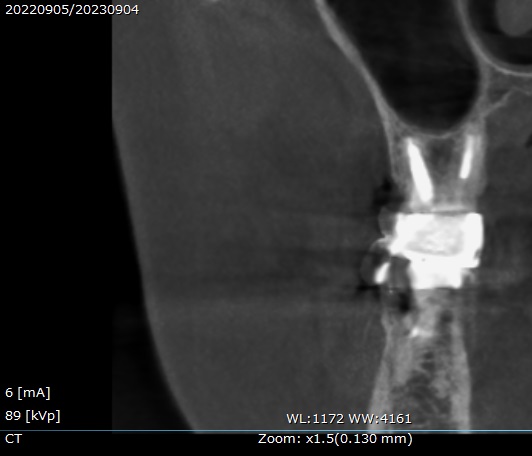

検診で来院された1年後に、新しくCTを撮影し状態を確認します。

1年後のCTの画像です。

正面からと、

横側からです☟

上顎洞の影が無くなっているのが分かります。

治療前と後の術前術後を比較してみましょう。

左上に撮影日の表示がありますが、

昨年2022年9月と、今年2023年9月のCT撮影です。

横側からの見た状態と、

正面からの状態。

矢印の場所の上顎洞の炎症が無くなり、本来の全体的に黒い空洞に戻っています。

治っていますね。

治療後のレントゲン写真では、根管にMTAセメントで充填してあり、

CTでは根の先まで白い詰め物がされているのが分かります。